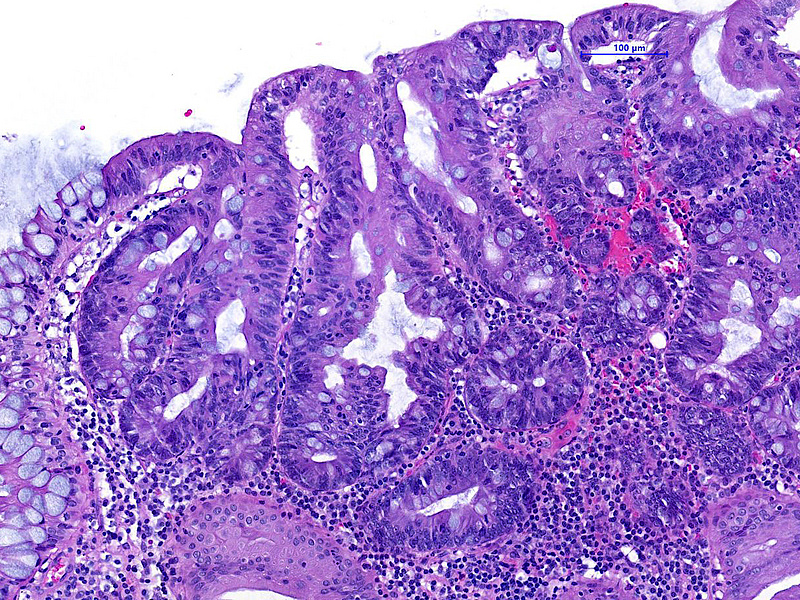

The ascending colon polyp is a serrated polyp characterized by a combination of two morphological patterns which are sessile serrated lesion (SSL) and traditional serrated adenoma (TSA). The former is formed by architecturally distorted serrated crypts with deep serrations, basal crypt dilatation and lateral growth along the muscularis mucosae (Panels A-B). Some foci of stromal proliferation resembling perineural cells are also seen within this component (Panel C). The TSA component has typical slit-like serrations, lined by tall columnar cells with intensely eosinophilic cytoplasm and pencillate nuclei (Panels D-E). Abrupt transition to dysplastic mucosa and glands are present, where the glands display more complex and crowded architecture with little intervening lamina propria (Panel F). The dysplastic cells show features of adenomatous dysplasia characterized by columnar cells with enlarged hyperchromatic nuclei, pseudostratification and reduced goblet cells (Panel G). In some areas, the cells display high grade cytology with more rounded nuclei and loss of polarity. MLH1 immunostaining was preserved in both the non-dysplastic and dysplastic glands with higher intense staining seen in the latter (Panel H).